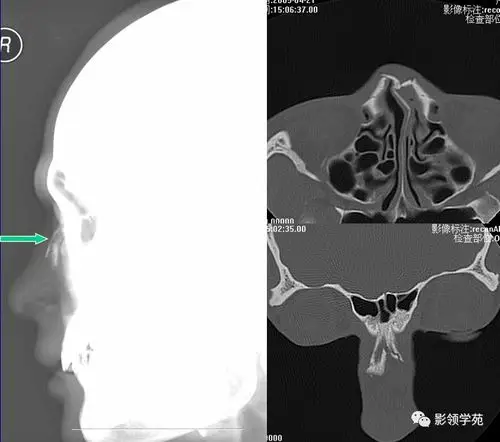

鼻骨骨折影像学诊断

鼻骨骨折影像学诊断与鉴别

鼻骨常见骨折征象

鼻梁上段塌陷或偏斜,皮下瘀血,x线鼻骨拍片或ct扫描可以显示骨折位置